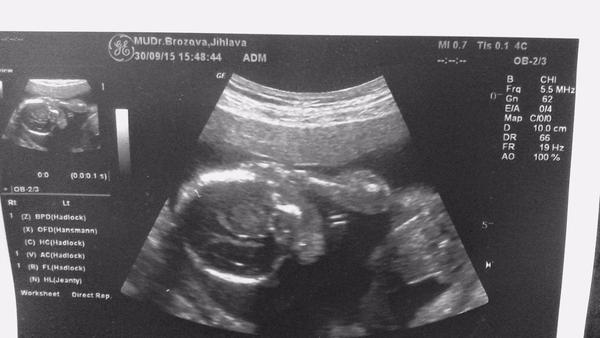

No prave něco tam visí ale co to je ze.Jinac foto je foceno tak ze dole je zadeček a nahoru vedou nozky

nejak se ve fotce neorientuju 😒 ...tady podle toho by to mel byt kluk nebo holka ?

@satynka Mně je pohlaví jedno 🙂. No ale jak jsem doma koukala na tu fotku, tak se mi taky zdá že to je kluk. Leda že by to byl kousek bříška, ale to se mi nezdá tak symetrické ( vyznačím to )...

@jadupka ty jo to je blba fotka.. Takhle to je kluk, prostě tam něco visí,ale stejně nevim z jakého úhlu na to kouknout..